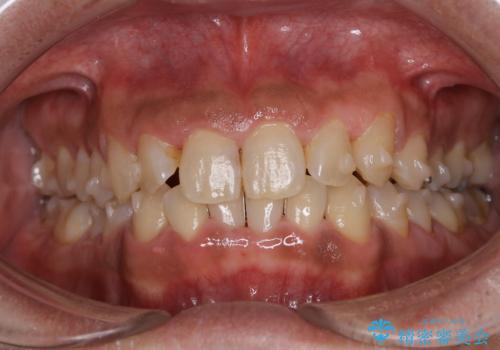

しぶといステインもエアフローワンで1日でキレイに!!

- インビザラインの治療中ですが、歯石やステインが気になるとのことでした。

コーヒーが大好きでよく飲むそうです。

全体的に歯石やステインが付着していたため、エアフロー60分コースを行いました。